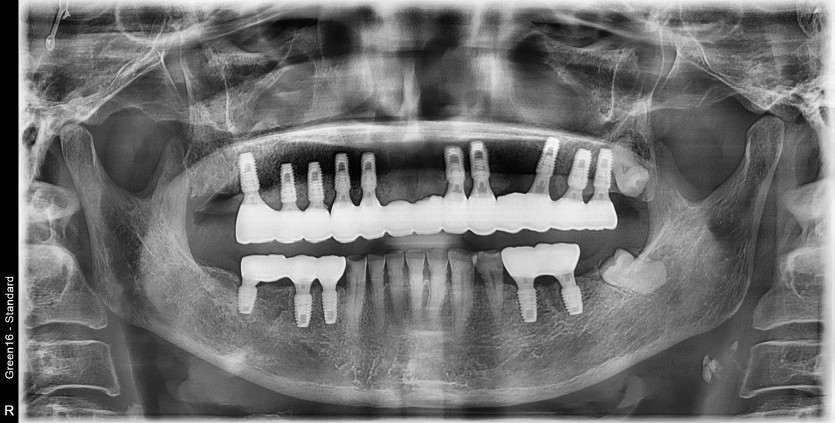

상악 전체 임플란트 증례입니다.(하악 일부)

15개의 임플란트로 완성하였습니다.